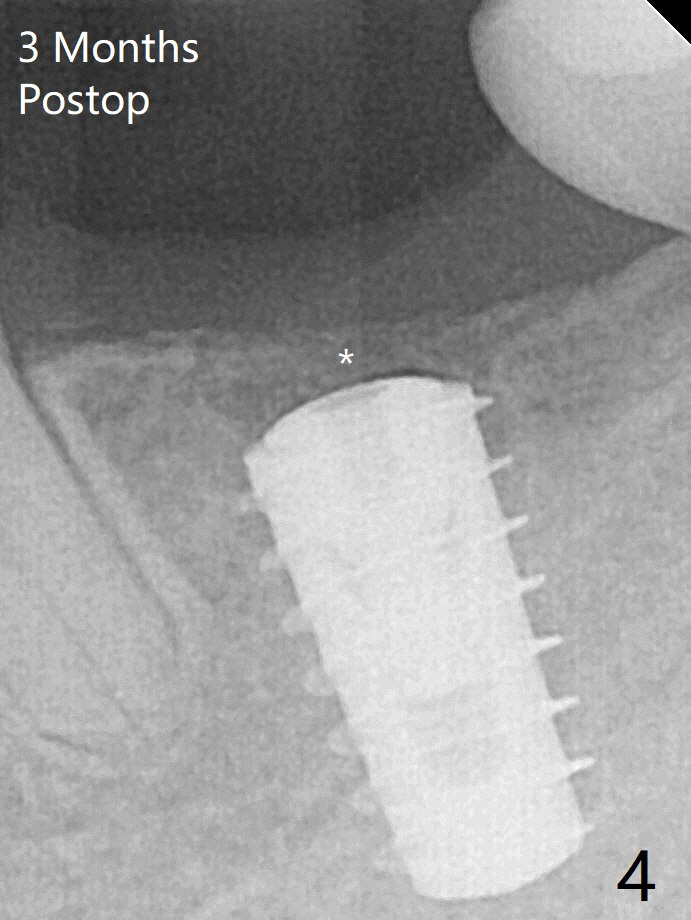

In contrast to #2 implant, the insertion torque of a 5x9 mm implant at #18 (Fig.1) is less than 10 Ncm because of depth difference between 2 implant systems. The design is for 5x10 mm. In fact each drill has its inherent 1.2 mm long tip. The 8.5 mm drilling depth is enough for 9 mm implant. The 2nd potential problem is that the implant may truncate a branch from the Inferior Alveolar Canal to the distal root of the 1st molar (Fig.2 (original design)). Ideally the implant should be placed distal and tilted mesial and short in length (Fig.3 (design to be improved)). A smaller implant may also help. A layer of new bone forms on the top of the implant 3 months postop (Fig.4 *). It is removed with surgical handpiece. After use of 5.6 mm profile drill, a 6x4 mm healing abutment is placed with minimal clearance from the mesial crest (Fig.5 *). A month later, a 5x4(3) mm pair abutment is seated apparently completely (Fig.6). A crown is delivered nearly 6.5 months postop (Fig.7 (mesial contact light)). The implant is subcrestal (*).